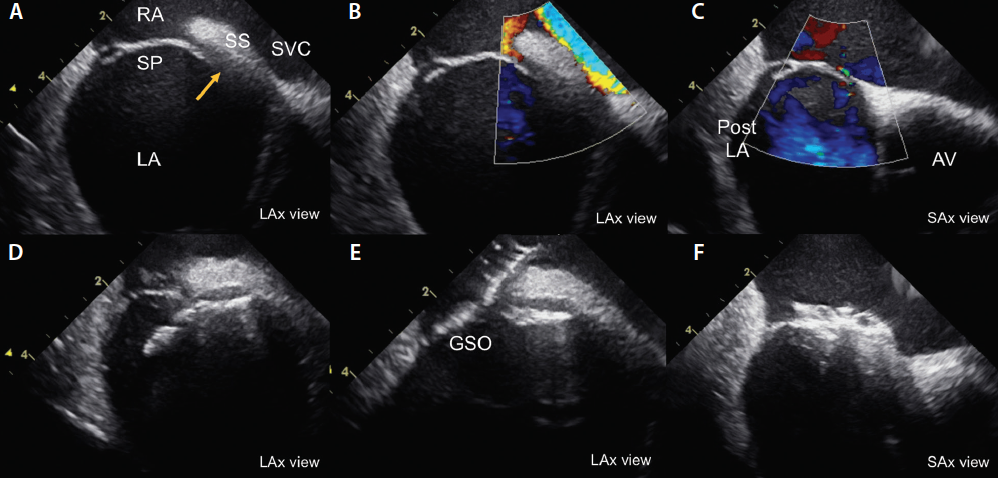

• From the home view, two key views can be obtained to guide PFO closure: (1) the septal (long-axis) view can be obtained by posterior tilting of the ICE probe using the anterior-posterior knob (Figure 1A and 1B); and (2) the aortic (short-axis) view can be obtained by slightly reducing the clockwise rotation of the entire probe and applying a slight right or left tilting using the right-left knob until the tip of the ICE catheter probe is inferior to the aortic valve, just above the tricuspid valve (Figure 1C).

Figure 1. ICE-guided PFO closure with a 25-mm Cardioform septal occluder. Two-dimensional and color Doppler ICE imaging of the PFO in the septal view (long-axis view) (A, B) and the aortic view (short-axis view) (C). Device deployment in the long-axis view (D, E). Final short-axis view after device deployment (F). AV, aortic valve; GSO, Gore Cardioform septal occluder; LA, left atrium; LAx, long axis; Post LA, posterior left atrial wall; RA, right atrium; SAx, short axis; SP, septum primum; SS, septum secundum; SVC, superior vena cava.

Interrogation of the septum and its adjacent structures in the short- and long-axis views allows a comprehensive survey of certain high-risk features of the PFO that may have important technical implications on the procedure. These high-risk features include the presence of a long PFO tunnel > 8 mm, concomitant atrial septal defect or fenestrated septum, atrial septal aneurysm, thick septum secundum, or prominent Eustachian valve or Chiari network.

We advance the deaired device delivery system over the Amplatz Extra Stiff wire into the left atrium and then remove the Amplatz Extra Stiff wire. The Cardioform septal occluder is typically preloaded into the delivery system, which minimizes the risk of air embolism. However, it is essential to maintain a wet-to-wet connection and avoid deep inspiration when an Amplatzer device is loaded into the delivery system because these situations carry a higher risk of air embolism. Once the device is advanced into the left atrium, the left-sided disc is unsheathed and pulled against the septum (Figure 1D). While maintaining a slight tug on the system, the right-sided disc is unsheathed/deployed, allowing the device to fully bracket the PFO.

The position and seal of the device are confirmed by two-dimensional and color Doppler ICE imaging in the short- and long-axis views. Device-specific securing mechanisms are then applied (tug test for Amplatzer and loop locking for Cardioform), and further evaluation with ICE is performed (Figure 1E and 1F). When satisfactory position, stability, and seal are ensured, the device is released under ICE and fluoroscopic guidance. The procedure is concluded by a final ICE survey with a clockwise sweep of the probe, starting at the home view to rule out pericardial effusion. Hemostasis can be achieved with a figure-of-eight 0 silk suture and additional manual pressure for 5 minutes.